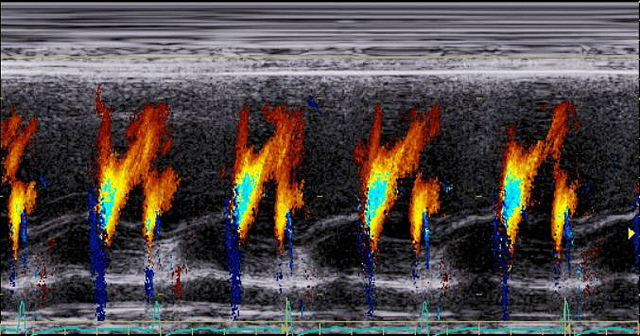

Sadie is her thirteen-year-old dog—beagle in the front and lab in back. She has been dying of congestive heart failure, which is the exact same thing stealing my mother-in-law’s life, moment by moment. It’s too ridiculous, this parallel, so we don’t speak of it. She’s just an old dog who also takes Lasik.

He leaves to get the chemicals and Sadie is panting very hard, as she had been the whole time. The vet explained that she is struggling for air as the fluid creeps up her lungs. Four weeks ago they had removed the fluid from Nora’s ‘plural effusion’. Nora and I called it “water in the lung.”